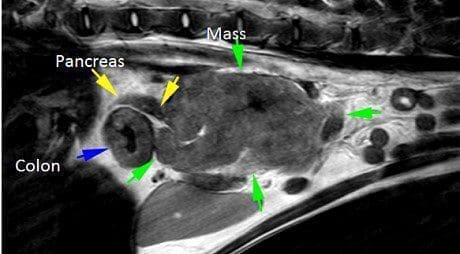

The MRI confirmed a multilobular irregular shaped mass in the cranial abdomen, which measures16cm (craniocaudal) x 6.9 cm (dorsoventral) x 8.0 cm (transverse). The mass surrounds the portal vein and branches of the portal system, the cranial mesenteric artery, and is resulting in a severe regional mass effect. The mass has a broad region of contact with the celiac artery, the distal ileum (at the level of the ileocolic junction), the caudal vena cava, and the ascending and transverse colon. At the level of contact with the colon, there is marked circumferential wall thickening, measuring up to 8 mm thick. There is also moderate diffuse thickening of the caecum. The margins of the pancreatic body and left pancreatic limb are in contact with this mass. Within the mid- to caudal aspect of the mass, there is marked narrowing of the portal vein and caudal vena cava. The jejunal lymph nodes are not seen. Multiple tortuous vessels are present along the periphery of the mass, most notable along the caudoventral margin. The pancreaticoduodenal vein is markedly tortuous, and subjectively enlarged, with a normal termination of the gastroduodenal vein into the portal vein. The right and left kidneys are moderately asymmetric, measuring 5.6 cm and 7.8 cm, respectively. The right kidney maintains a normal shape and similar signal intensity to the left. The adrenal glands are seen and unremarkable.

Diagnosis: Inoperable mesenteric mass involving major vessels and intestine

Large, extensive, mesenteric mass, with involvement of the ileocolic junction, transverse

colon, and perivascular involvement of the portal vein, caudal vena cava, and cranial

mesenteric artery. Organs of origin include colon/ileum, mesenteric, or lymph node (pancreas is possible).

There is evidence of collateral portal-portal venous shunting. The colonic and caecal wall thickening may be secondary to lesion extension, or regional oedema, inflammation, or haemorrhage. The T2 and STIR hyperintensity within the mass may represent necrosis, haemorrhage, or lymph.